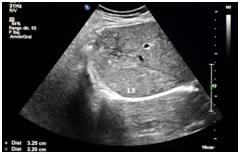

Male patient of 37years of age , white race, resident in Habana del Este municipality of Havana province, with previous health history that comes to consultation for presenting prolonged febrile syndrome with 56days of evolution, febrile peaks of 38‒39 degrees, accompanied by chills and decay. Urinary sepsis was determined as initial diagnosis so antimicrobial treatment was imposed for 10 days. There is no improvement in the clinical picture and the febrile symptoms persist. The patient is admitted to the hospital service of the Central Hospital in Havana. On physical examination, painful abdomen on palpation in the right hypochondrium and epigastrium without other alterations Laboratory tests are performed or presenting Haemoglobin: 12gl, Leucogram which yields an Eosonophilia of 66% and an Erythrosedimentation: 67. Serial blood cultures and urine cultures they were negative. Likewise, the serology was negative. Within imaging studies abdominal ultrasound reporting hepatomegaly that exceeds be 2 cm costal margin with the presence of a hypo echoic image with nodular, peripheral tendency without flow Doppler level right lobe study (Figure 1) interpreting c indicated omo pyogenic liver abscess therefore imposes treatment with antimicrobial therapy (Metronidazol EV) (Figure 1). Ultrasound: nodular, hypoechoechoic, peripheral, non‒vascularised image at the level of the right lobe of the liver clinically the patient improved his general condition, but he kept the febrile syndrome accompanied by diffuse abdominal pain. By keeping the same ultrasound image last month of treatment study it was conducted by T omografía who reported abdominal the presence of density areas of irregular appearance, in the right lobe of the liver in segments VII and VIII and endovenous study showed lesions with poor contrast capitation both Portal and late phase (Figure 2). Computed tomography with intravenous contrast: hypo dense areas of irregular appearance at the level of segments VII and VIII of the liver with poor contrast uptake Ultrasound images suggested the diagnosis of parasitosis Fasciola hepatica but also by positron raised the differential diagnosis of Focal nodular hyperplasia at que sugi river echo directed FNA that reported cytological Negative of neoplastic cells and inflammatory infiltrate with abundant eosinophils. Given this possible diagnosis, endoscopy was performed, which reported alkaline pangastropathy with a duodenal swab for negative parasitological study. Conical crown was made on several occasions resulting negative and biliary drainage was indicated to be not useful for diagnosis. In view of Clinical and Imaging suspicion of Fasciola hepatica, it was decided to perform a weekly evaluative ultrasound for 4 more weeks, observing at the end of the fourth week echogenic images, elongated with movements inside the gallbladder and an echogenic image without acoustic shadow in the canal. Coledochus suggesting the diagnostic imaging of adult Fasciola parasites in the bile ducts (Figure 3). Evolutionary ultrasound: echogenic images, free, with movement at the level of the gallbladder. The patient was referred to the Institute of Tropical Medicine (IPK) where the diagnosis was verified, imposing treatment with a single oral dose of Triclabendazole with excellent therapeutic response.

Figure 2 Computed tomography.

Computed tomography

In Fasciolosis hepatica, it can present as nodular or tortuous lesions, with enhancement after variable contrast, although in 80% it allows its better delimitation in late phases. However, the most characteristic of these lesions is their sub capsular location, with tortuous paths that adopt a centripetal direction in the direction of intrahepatic bile ducts, whose appearance makes some authors propose it as highly suggestive of Fasciolosis (Figure 2).16–18 Hepatic capsule enhancement with contrast injection is also described, which correlates with thickening and inflammation of the capsule observed in laparoscopy. Another element to consider is the sub capsular hematoma, an infrequent complication, but one that undoubtedly requires imaging control. In relation to biliary fasciolosis, the role of CT in its diagnosis is smaller, being able to only show minimal dilation of the extra hepatic bile duct, being a non‒specific finding.17 In the patient reason for discussion, both Tomography and Ecography could be useful, the latter being the one that contributed most to the definitive diagnosis, coinciding with the findings reported in the literature according to the clinical phase of the disease.